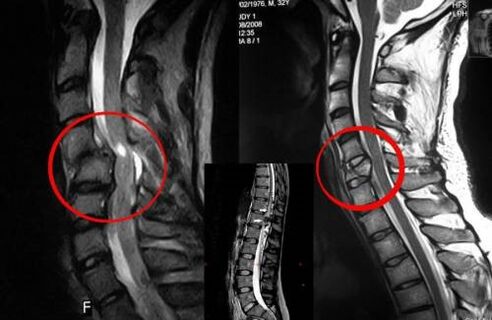

Diagnostic

L'ostéochondrose vertébrale nécessite une consultation rapide avec un médecin qui aidera à restaurer le dos endommagé. Les appareils modernes permettent un diagnostic dès les premiers stades de développement. En cas de pathologie, contactez un neurologue ou un orthopédiste. Tout d'abord, un examen de la colonne vertébrale blessée est effectué et une anamnèse est effectuée, puis des méthodes de diagnostic en laboratoire et instrumentales sont prescrites pour détecter l'ostéochondrose :

- radiographie;

- myélographie;

- examen neurologique;

- TDM et IRM ;

- Résonance magnétique nucléaire.